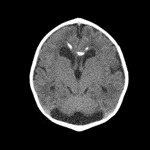

Using Magnetic Resonance Imaging (MRI) to scan the brain and using the image to identify whether the patient has a brain tumor or not is the common way doctors use it today. However, as this may potentially add to the workload of healthcare professionals, it becomes crucial to explore methods for automating image identification. One effective algorithm for this purpose is the utilization of a Convolutional Neural Network (CNN) network. However, when applying a CNN network to discern whether an individual has meningioma or not, it becomes evident that the available data may be limited. Meningioma is relatively uncommon, and not all associated images have been made accessible for analysis. The shortage of original samples makes it hard to train the CNN network and has relatively low accuracy. In this case, this study tries to use DCGAN to generate more images based on the original sample. By comparing the accuracy and f1 score of the CNN network, this study finds that implementing images has improved the performance of the CNN network. By implementing the images, the DCGAN generates, the accuracy for the same CNN network to identify whether the images have meningioma or not is increased from 93.53 percent to 97.75 percent. The f1 score also increased from about 0.9187 to about 0.9738.